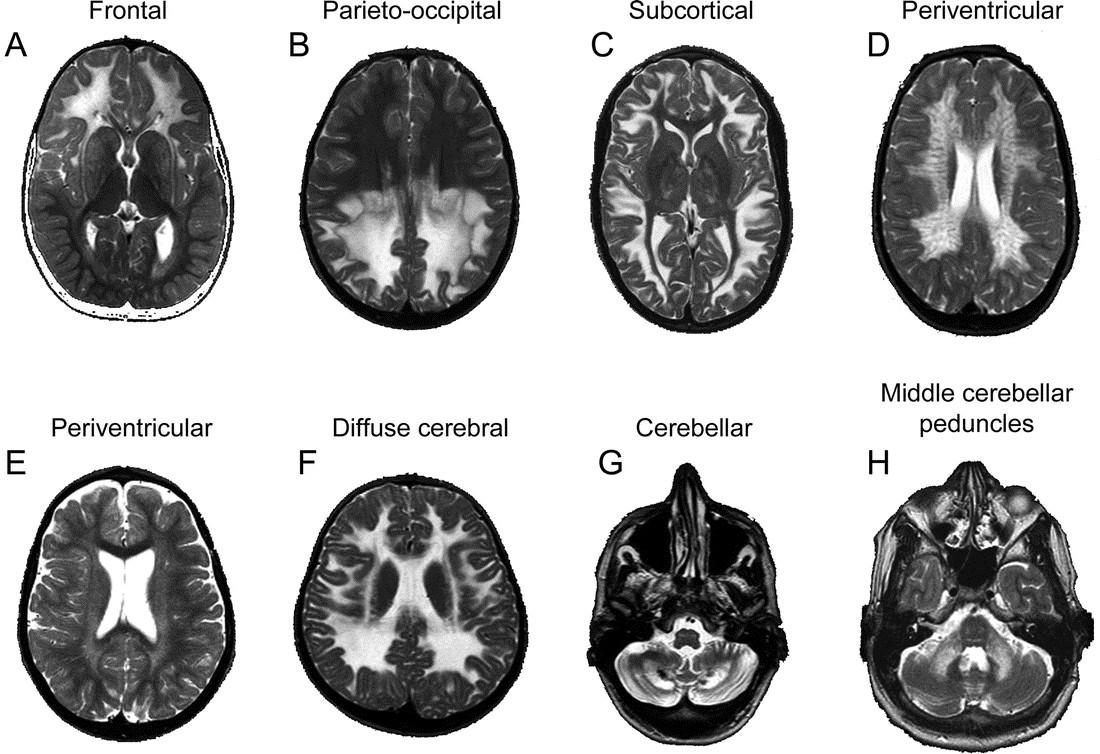

Patterned Approach Patterned Approach

Other Things to Look For Other Things to Look For

• Subcortical U-fibers: Involved or spared? Subcortical U-fibers: Involved or spared?

• Gray matter involved? Gray matter involved?

• Brainstem involved? Brainstem involved?

• Macrocephaly? Macrocephaly?

• Leading edge of enhancement? Leading edge of enhancement?

Abnormal MR spectroscopy (e.g. NAA, lactate)?

Deep WM Predominant Deep WM Predominant (Subcortical U-Fibers Spared) (Subcortical

U-Fibers Spared)

• Thalami involved? Thalami involved? YES YES

• Lysosomal storage disorder Lysosomal storage disorder

• Krabbe Krabbe

• Gangliosidosis (GM-1, GM-2) Gangliosidosis (GM-1, GM-2)

• Thalami involved? Thalami involved? NO NO

• Brainstem involved? Brainstem involved? YES YES

• X-linked adrenoleukodystrophy (ALD) X-linked adrenoleukodystrophy (ALD)

• Brainstem involved? Brainstem involved? NO NO

• Metachromatic leukodystrophy Metachromatic leukodystrophy

• Mucopolysaccharidoses (e.g. Hunter’s, Hurler’s) Mucopolysaccharidoses (e.g. Hunter’s, Hurler’s)